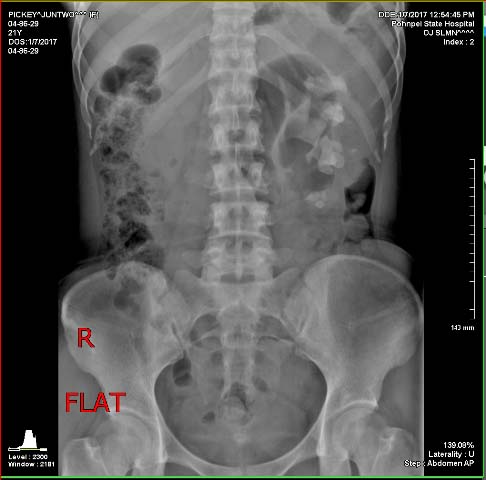

Röntgenbild von Juntwo: Von vorne gesehen rechts die weissen Flecken in

Hüfthöhe, das sind die großen Steine in der Niere, die durchbrachen und Blut

in den Körper strömen lassen. Die Ärzte gaben ihr nur noch wenige Tage

zum Überleben.